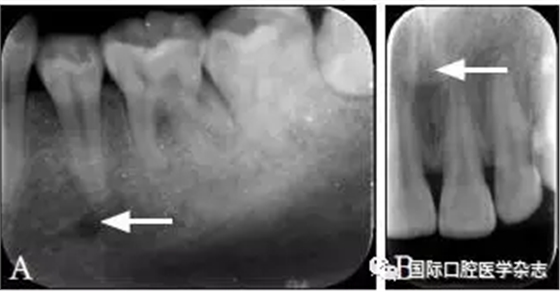

因拍攝角度的不同,頦孔和切牙孔影像可能與根尖重疊(圖8),應(yīng)注意觀察牙根的牙周膜及骨硬板是否連續(xù),或重新偏角拍攝X線片以確認(rèn)其與牙根的關(guān)系。

圖 8 頦孔(A)和切牙孔(B)

Fig 8 Mental foramen(A) andincisive foramen(B)